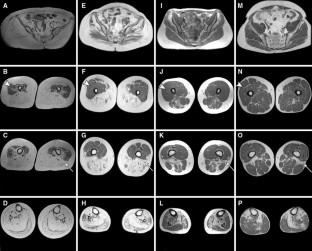

GNE myopathy (MIM 600737) is an autosomal recessive muscle disease caused by mutations in the UDP-N-acetylglucosamine 2-epimerase/N-acetylmannosamine kinase (GNE) gene. Besides the typical phenotype, characterized by the initial involvement of the distal leg muscles that eventually spreads proximally with sparing of the quadriceps, uncommon presentations with a non-canonical clinical phenotype, unusual muscle biopsy findings or both are increasingly recognized. The aim of our study was to characterize the imaging pattern of pelvic and lower limb muscles in GNE myopathy, thus providing additional diagnostic clues useful in the identification of patients with atypical features. We retrospectively evaluated muscle MRI and CT scans of a cohort of 13 patients heterogeneous for GNE mutations and degree of clinical severity. We found that severe involvement of the biceps femoris short head and, to a lesser extent, of the gluteus minimus, tibialis anterior, extensor hallucis and digitorum longus, soleus and gastrocnemius medialis was consistently present even in patients with early or atypical disease. The vastus lateralis, not the entire quadriceps, was the only muscle spared in advanced stages, while the rectus femoris, vastus intermedius and medialis showed variable signs of fatty replacement. Younger patients showed hyperintensities on T2-weighted sequences in muscles with a normal or, more often, abnormal T1-weighted signal. Our results define a pattern of muscle involvement that appears peculiar to GNE myopathy. Although these findings need to be further validated in a larger cohort, we believe that the recognition of this pattern may be instrumental in the initial clinical assessment of patients with possible GNE myopathy.

Fig. 1